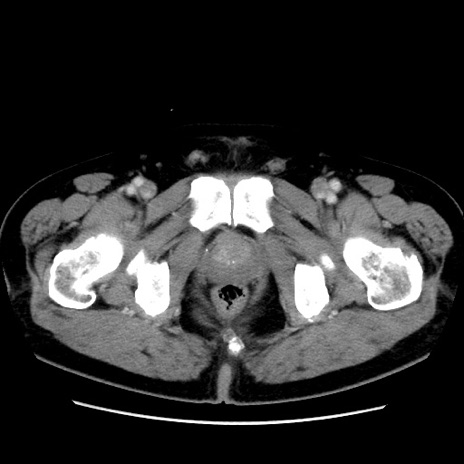

冠状断像